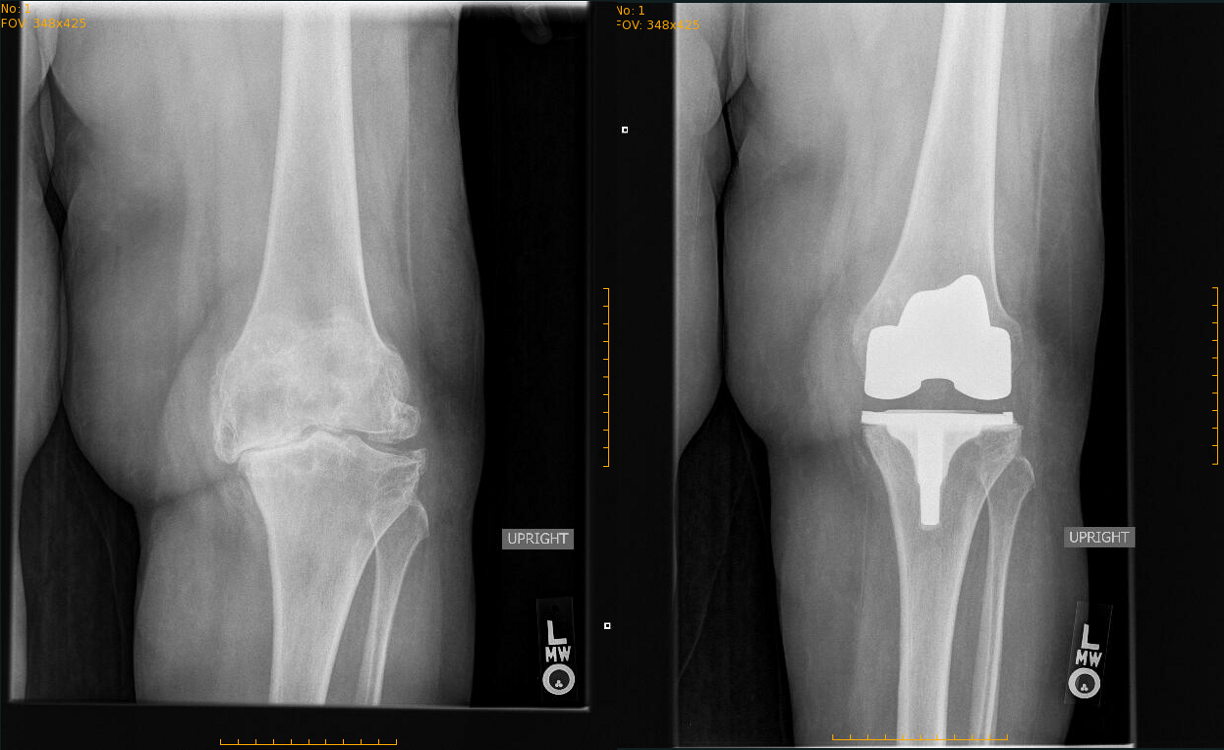

Case study

Before and after pictures of a knee replacement of a very arthritic knee that I treated with knee replacement.